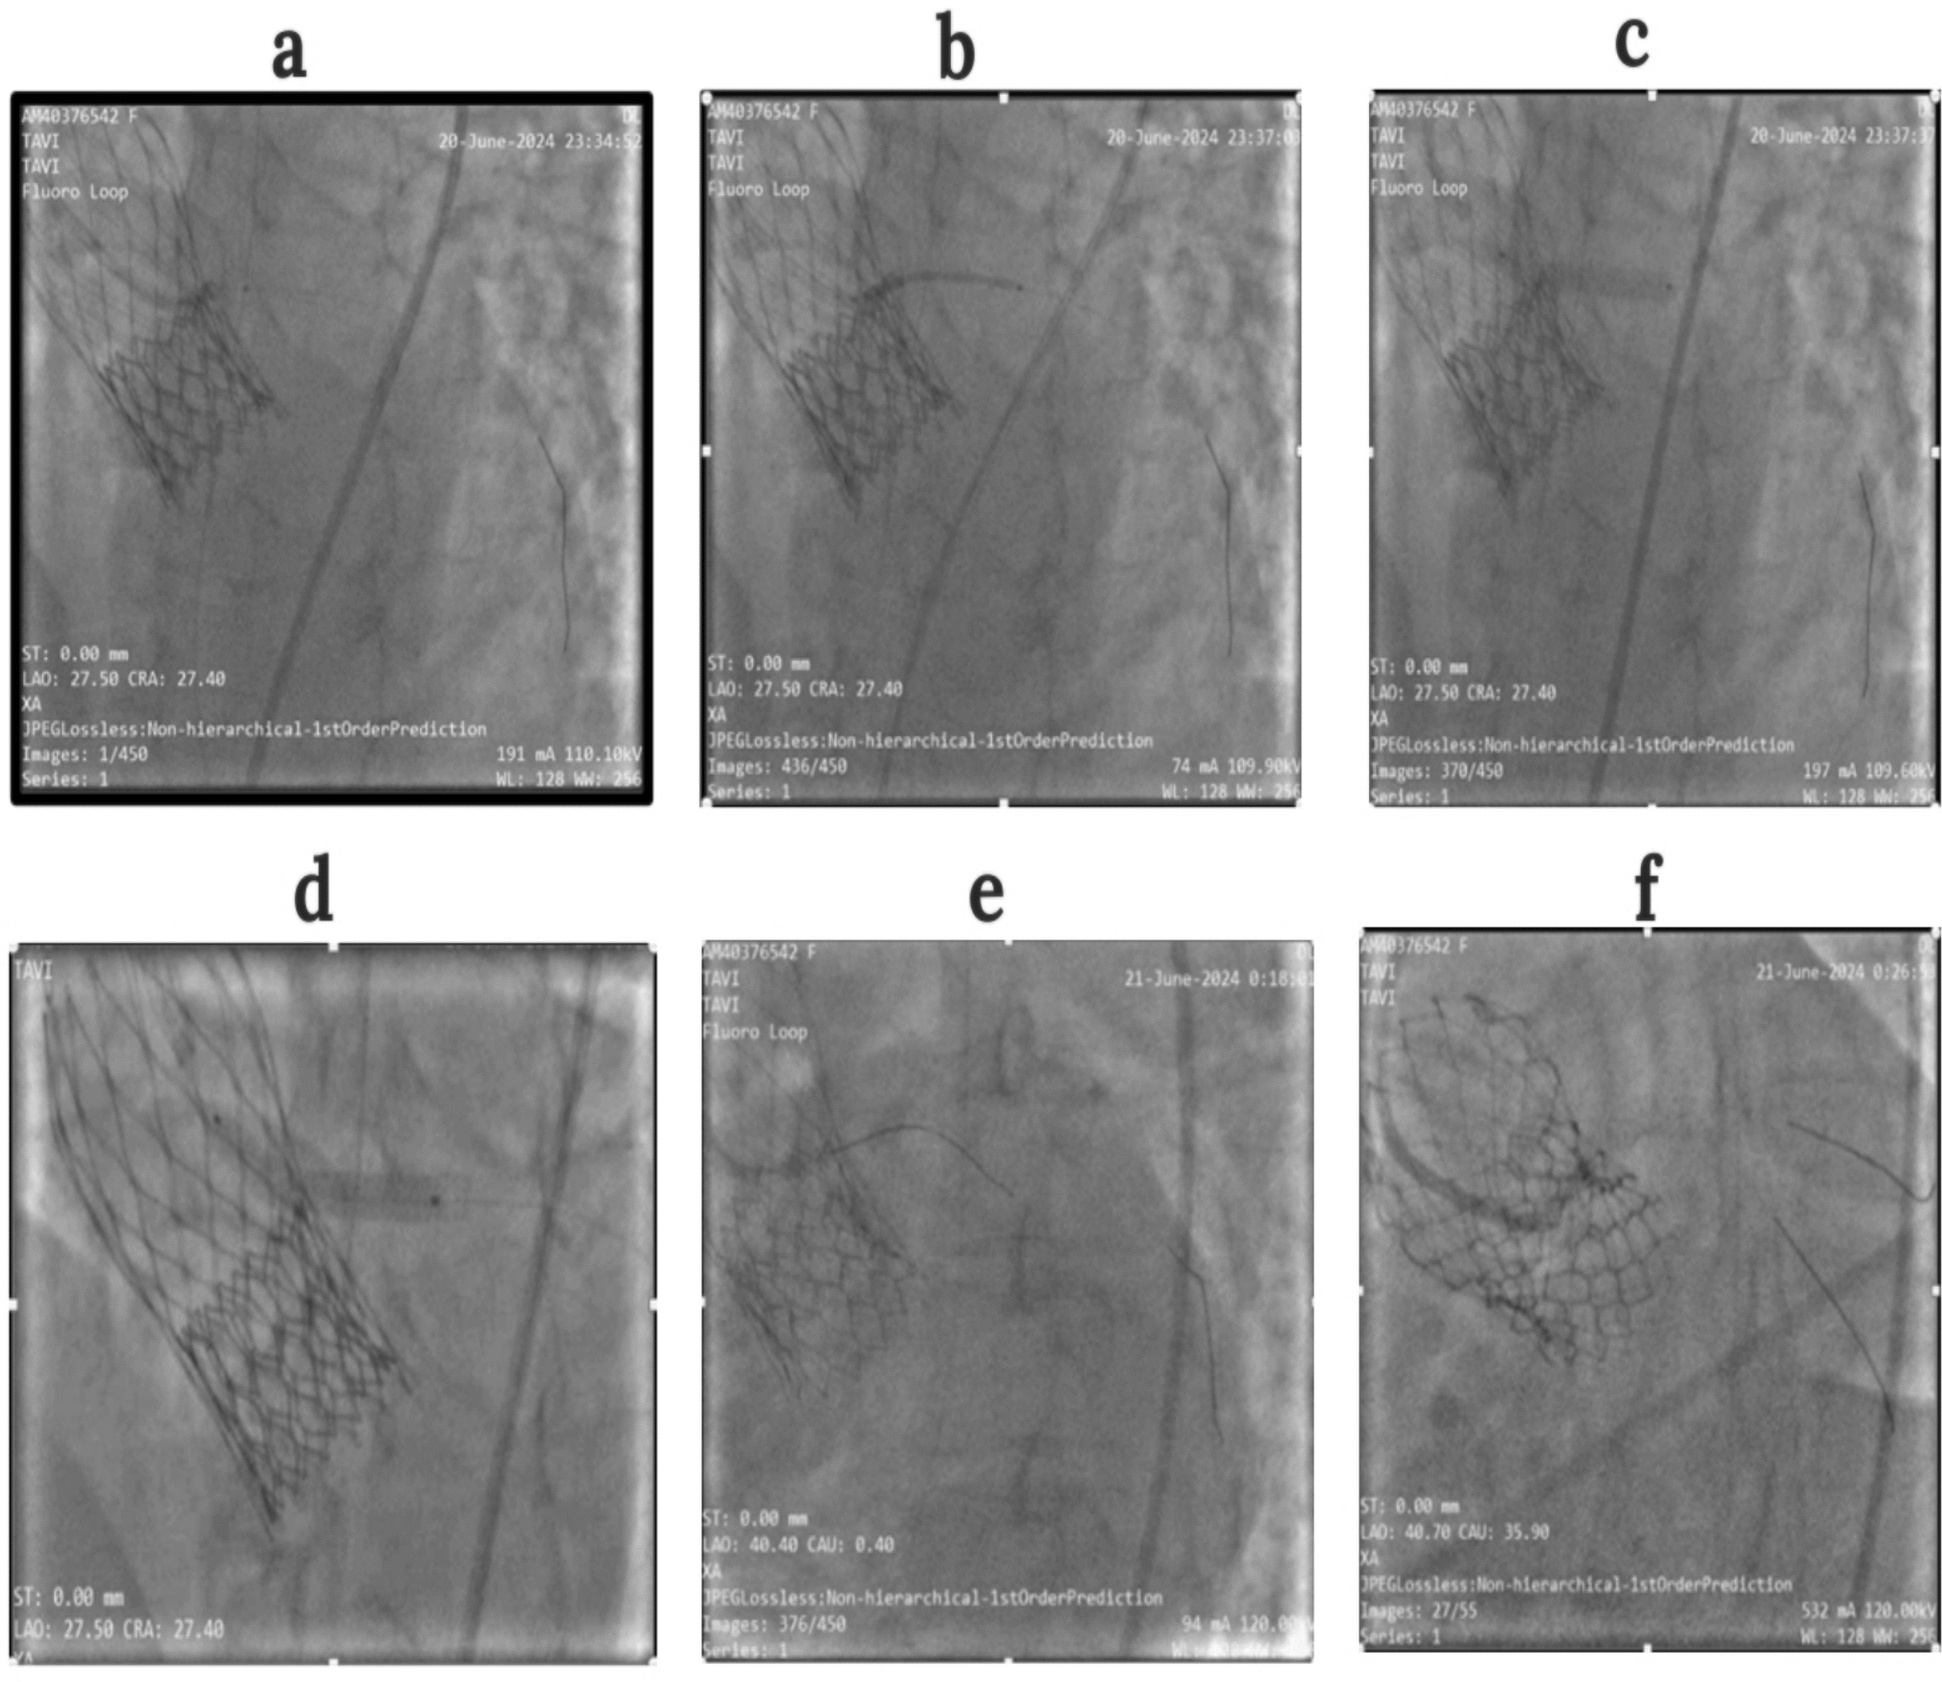

Case presentation: We report the case of a 68-year-old female patient of Indian ethnicity with prior transcatheter aortic valve implantation using a 26 mm CoreValve (Medtronic), presenting with symptomatic valve degeneration. Her case having been deemed high-risk for open surgical intervention, she was selected for a transcatheter aortic valve implantation-in-transcatheter aortic valve implantation procedure. Preprocedural computed tomography imaging showed a critical risk plane for the left main coronary artery, necessitating coronary protection. A 23 mm balloon-expandable Myval transcatheter heart valve was implanted using transfemoral access. Coronary protection was initiated with prepositioning of a coronary guidewire in the left coronary artery. Following valve deployment, the patient developed hypotension with left main coronary artery flow compromise, requiring bailout left main coronary artery stenting, resulting in a chimney configuration. Postdeployment angiography confirmed optimal valve positioning with preserved coronary flow. The patient initially developed hypotension and severe hypokinesia, which was managed successfully with emergency left main coronary artery stenting and supportive care. She exhibited immediate hemodynamic recovery and was discharged in a stable condition. This is the first documented case of a Myval-based transcatheter aortic valve implantation-in-transcatheter aortic valve implantation with left main coronary artery chimney stenting from East India.